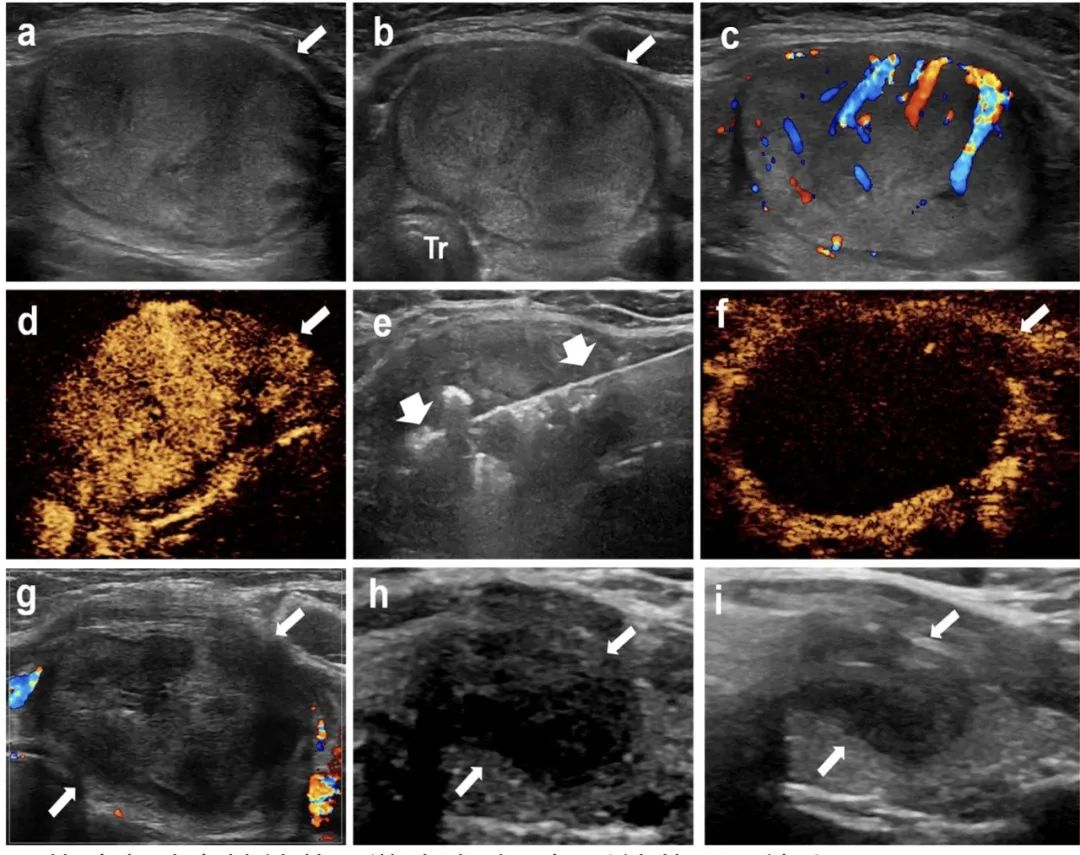

甲狀腺左葉實(shí)性結(jié)節(jié),微波消融4年后結(jié)節(jié)明顯縮小